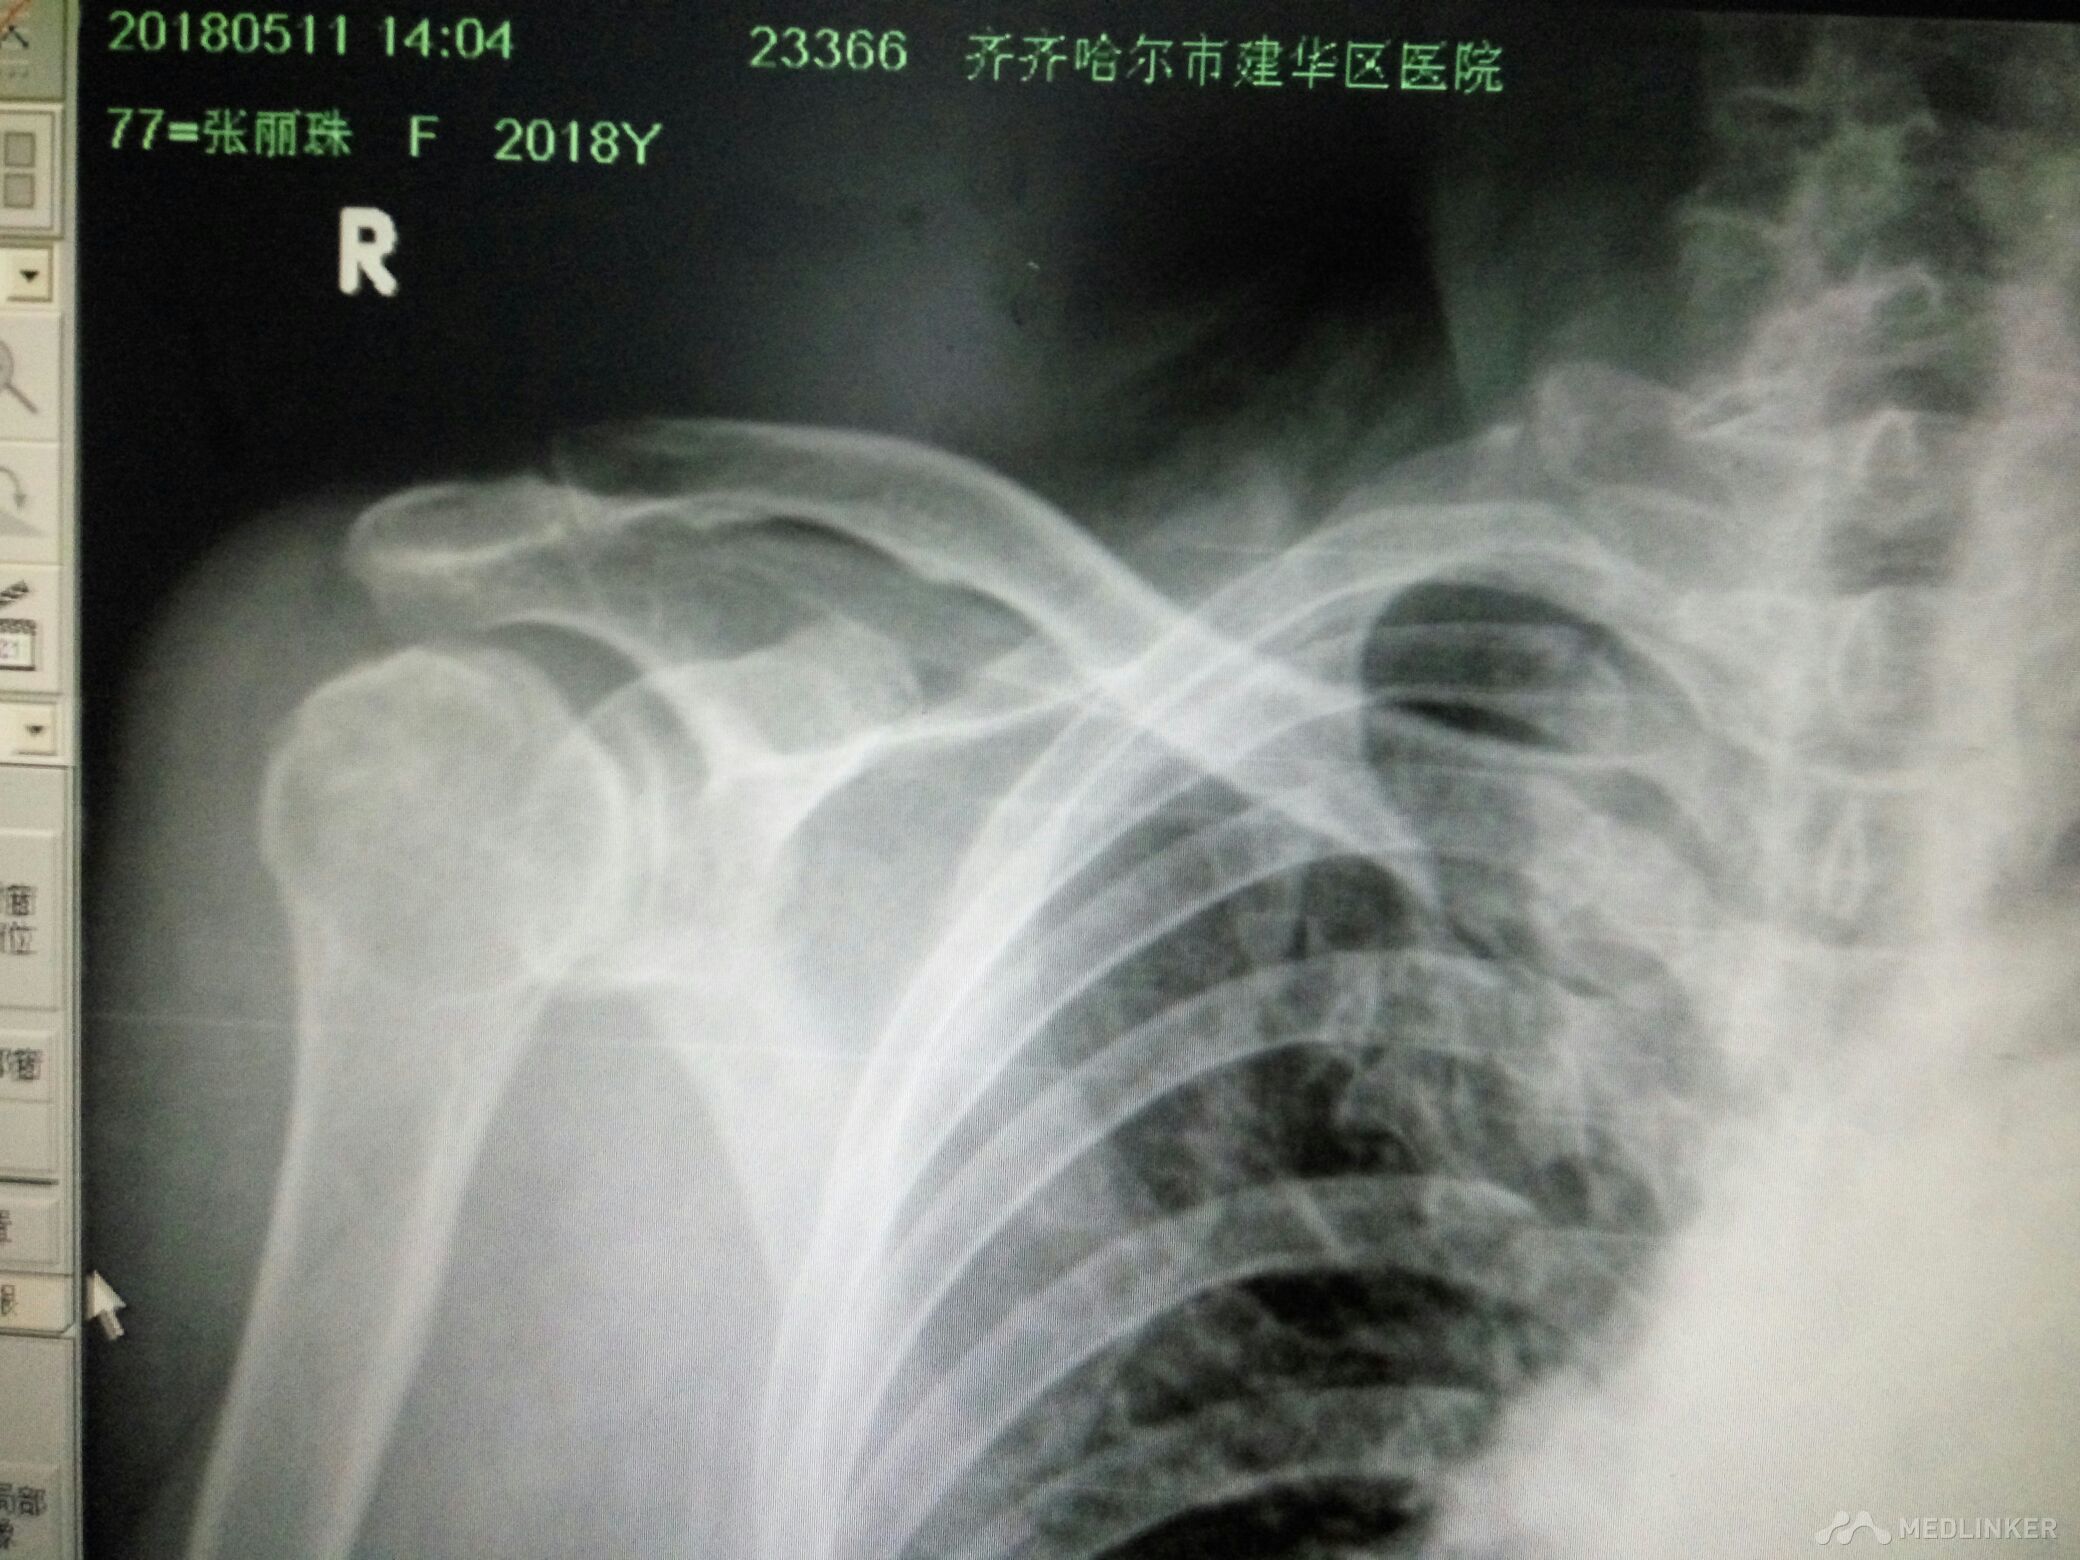

右肩关节脱位并肱大结节撕脱性骨折

该患者女77岁不慎跌倒所致肩关节活动丧失局部疼痛来齐齐哈尔市解放门医院骨科经张立群医生诊断肩关脱位拍片检查右肩关节脱位并肱骨大结节骨折经手法整复后拍片检查复位成功肱骨大结节骨折对位对线良好。